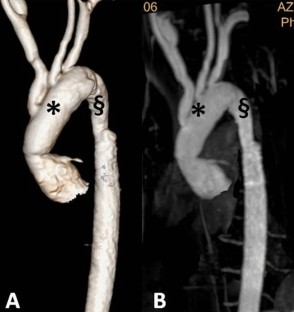

Fig. 3